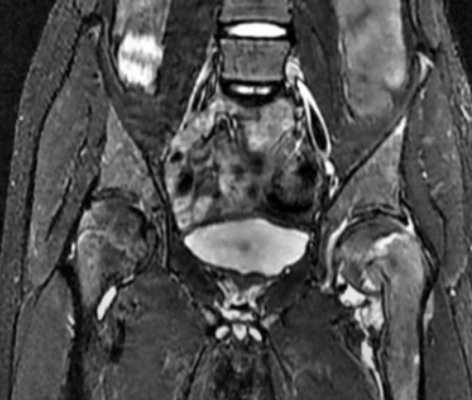

На снимке показан пример ишиофеморального импинджмента в хронической форме. Пациент - женщина в возрасте 60 лет. Жалобы - постоянные болевые ощущения в тазобедренных суставах, наиболее проявляющиеся в правом.

Гипертрофия седалищных бугристостей, ведущая к значительному сужению ишиофеморальных пространств; наблюдается деформация, отеки, несущественные скопления жидкости в квадратных бедренных мышцах (максимально заметные справа), неравномерная атрофические изменения с характерной жировой инфильтрацией.